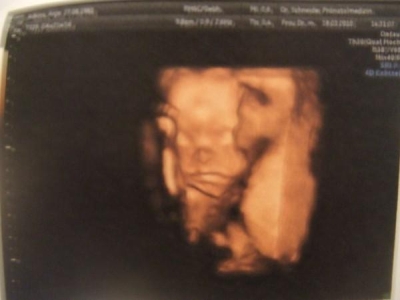

| March 25th 2007: Did you ever try to walk around as less as possible for a couple of weeks? If not, don't. - It really, really sucks. The sun is shining and it looks like it's finally getting spring, and I can't even leave the house. :( I'm still having contractions, but got medicine for it now, so it got a little better. Walking around too much (which is not much at all) still makes it worse though. On the other hand, it's only a couple of weeks before it all will be over and we're going to be parents :). The baby is doing fine. We are 99.9% sure at this point what the gender is, but I still don't want to write it down on this page since a lot of people from my family want it to be a surprise. You can always ask me if you want to know though :) During the last ultrasound (in week 31) they messured the baby and it turns out that "it"'s 37cm tall and weighs over 1000gr (I think it was somwhere around 1500, but I don't remember, I am bad with numbers :) ). Healthwise everything is fine too, 5 fingers and 5 toes on every hand/foot, 2 eyes, ears, a cute little nose (the baby was actually sucking it's thumb during the last 3D ultrasound - it was soooo cute), a healthy heat and all the other organs and bones are where they should be. So as far as the doctors can tell everything is perfekt. I can't believe it's only going to be 64 more days till the baby will be here (that's counting till the latest date, May 28th, but they said it might be as early as May 11th, so it's probably not even going to be 64 more days). I just hope we'll be able to find an appartment and move in before the baby gets's here. But no matter what, I am all kinds of excited and I can't wait :) |